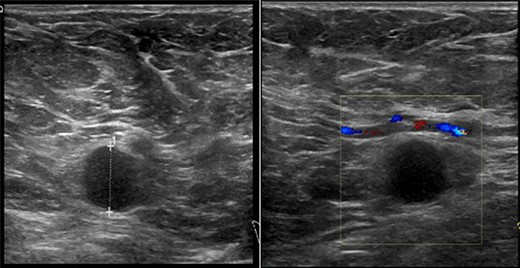

On clinical examination, there were tender nodularities in the upper outer quadrant of the right breast. The nipple looked thick and tender at the nipple tip, with punctate bleeding from different sites (P3) (Fig. 1). Examination on the left breast and both of the axillae were unremarkable. The mammogram reported segmental distribution of pleomorphic calcification on the right breast, which was widespread and was measuring up to 11 cm from the nipple posteriorly. The appearances of the calcifications were suspicious for malignancy (M4). There were benign appearing calcifications on the left breast as well (M2) (Fig. 2). On ultrasound (US), there was no discrete mass or suspicious feature seen in the right upper outer quadrant. However, there was a 10-mm deep-seated, round, abnormal-looking lymph node on the right axilla (U4), which could not be biopsied at the time due to a pulsating blood vessel overlying it [1] (Fig. 3).